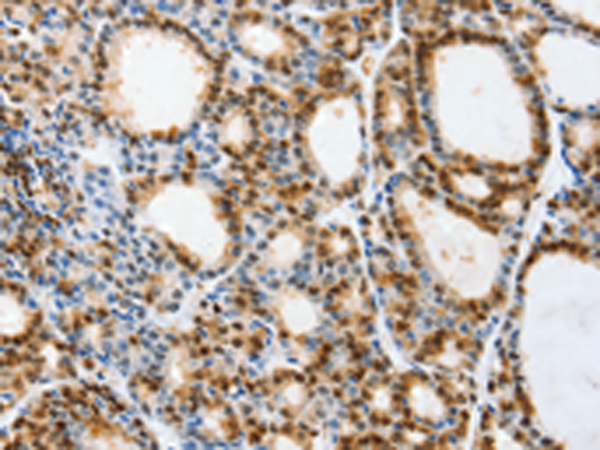

分类: 科研抗体货号: P11147别名: TYH; DYT14; DYT5b应用: IHC反应种属: Human